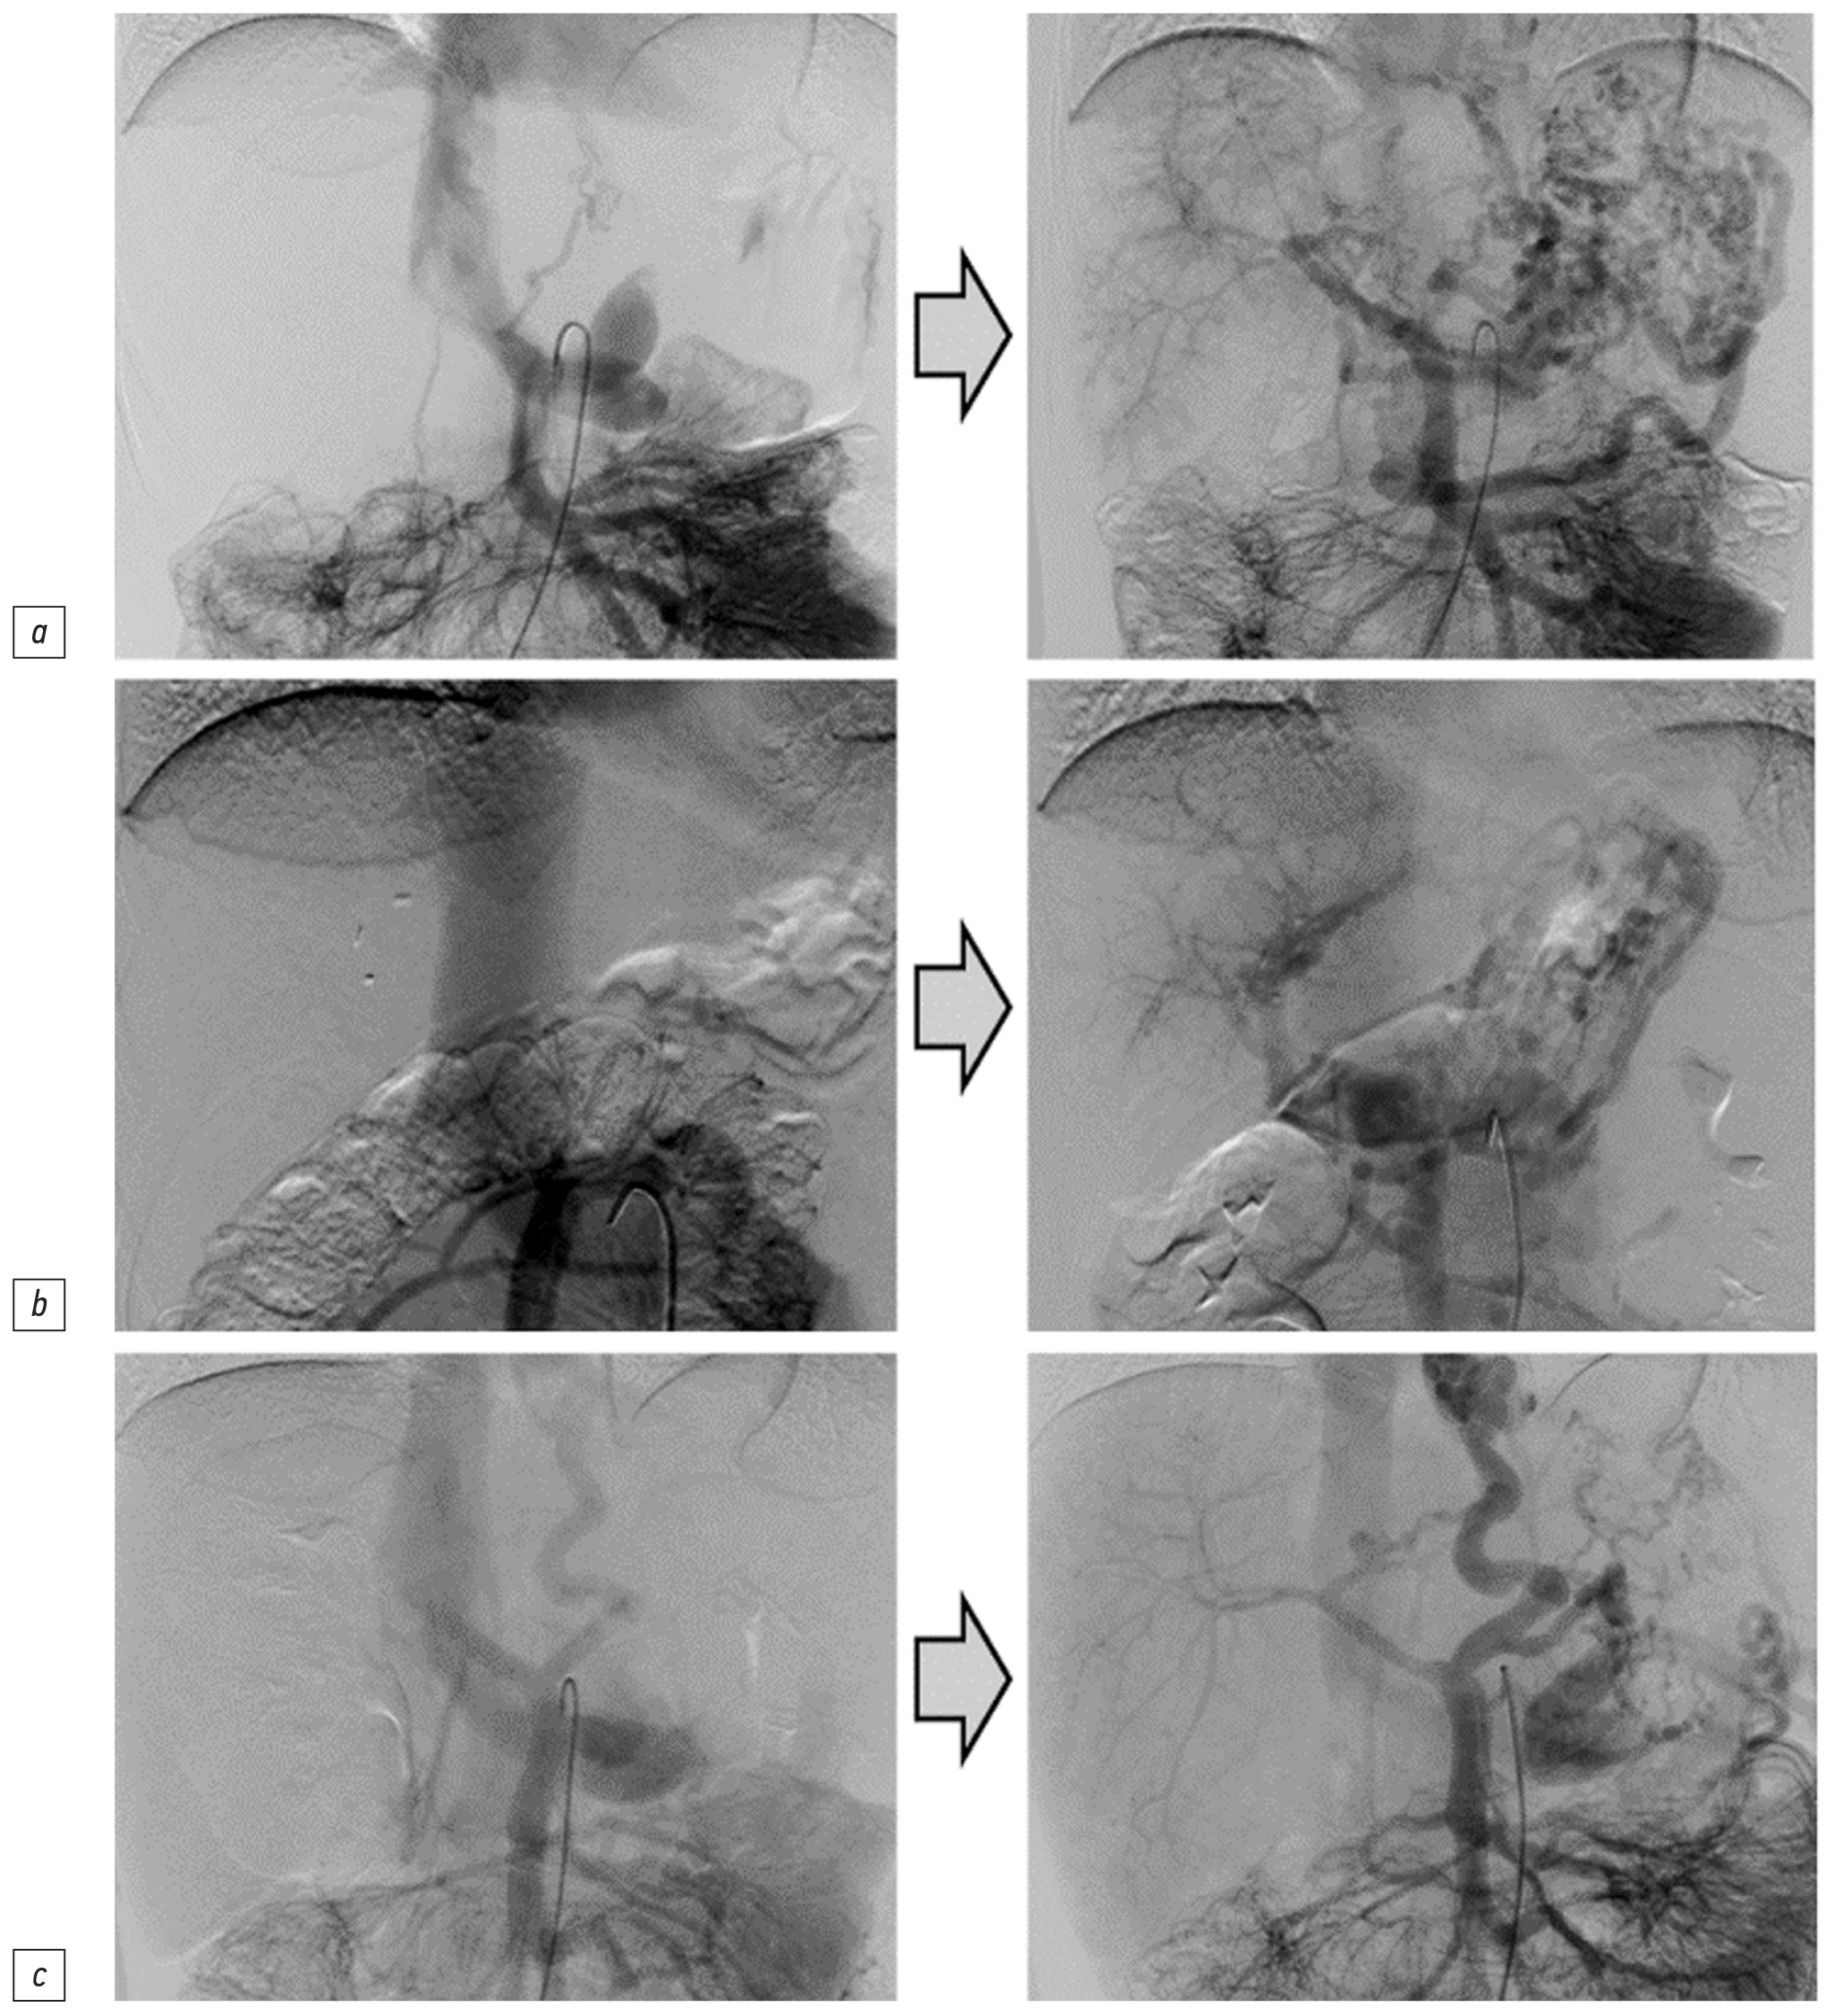

Данные ангиографии до и после реконструкции шунтов сравнивали у 32 детей — улучшение ППП наблюдалось у 78% (n=25), а у остальных 22% (n=7) ППП не менялась (рис. 2).

Рис. 2. Ангиограммы (венозные фазы целиакографий) до и после операции с улучшением портальной перфузии печени: a — мальчик 7 лет, b — девочка 11 лет, c — девочка 7 лет.

Fig. 2. Angiograms (venous phases of celiacography) before and after surgery with improving of portal perfusion of the liver: a — boy, 7 years old, b — girl, 11 years old, c — girl, 7 years old.